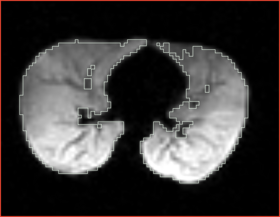

* Correction of the bias in vervet MRI. Acquisition parameters: 3T GE scanner, single-channel dedicated RF coil (Litzcage, Doty Scientific, Columbia, SC); 3D SPGR sequence (TI 600ms, TE 3.276ms, TR 15.28ms; flip angle 15 deg; matrix 256x256; FOV 12cm; in-plane resolution 0.47 mm; slice thickness 0.5 mm). | * Correction of the bias in vervet MRI. Acquisition parameters: 3T GE scanner, single-channel dedicated RF coil (Litzcage, Doty Scientific, Columbia, SC); 3D SPGR sequence (TI 600ms, TE 3.276ms, TR 15.28ms; flip angle 15 deg; matrix 256x256; FOV 12cm; in-plane resolution 0.47 mm; slice thickness 0.5 mm). | ||

- Correction of the bias in vervet MRI. Acquisition parameters: 3T GE scanner, single-channel dedicated RF coil (Litzcage, Doty Scientific, Columbia, SC); 3D SPGR sequence (TI 600ms, TE 3.276ms, TR 15.28ms; flip angle 15 deg; matrix 256x256; FOV 12cm; in-plane resolution 0.47 mm; slice thickness 0.5 mm).